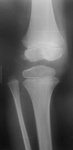

Мальчик 11 лет, жалобы на боли в коленных суставах в утреннее время. Движения в полном объеме, безболезненные, варусная деформация голеней с обеих сторон. У отца и деда выраженый гоноартроз.

Вопрос к детским рентгенологам (сама с детьми не работаю)-"лохматость" контуров суставных поверхностей бедренных костей у деток должна быть? А потом мне какие дополнительные тени кажутся, как суставные мыши у взрослых.

Костная структура соответствует возрастной норме. Единственное, что настораживает, великоват диастаз в межберцовом сочленинии. Я бы выполнила сравнительную рентгенографию обоих коленных суставов в прямой проекции с очень небольшой внутренней ротацией голеней 1 лучом на 1 пленке (с обязательным строгим соблюдением симметрии в укладке).

Костный возраст не соответствует 11 годам, по Садофьевой:

Полное окостенение эпифизов бедренной, большеберцовой и малоберцовой костей завершается несколько раньше (примерно в 8 лет)

Головки малоберцовок - как-то высоковато стоят по прямым снимкам, то ли укладка такая.

Вот-вот, и я об этом же. Дополнительные тени и нечеткость контуров.

Согласна, суставы не соответствуют возрасту, дополнительные тени - это добавочные ядра окостенения. Малоберцовые кости какие то длинные, щели межберцовых суставов широкие (в норме малоберцовая кость накладывается на большеберцовую). Вообщем, какие то диспластичные суставы. Костно-травматических изменений нет.

подозрение здесь на 2сторонний рассекающий остеохондрит ,ко-ый может иметь место в 30% случаев .слева в проекции дистального эпифиза бедра ,в проекции латерального мышелка бедра ,определяются точки окостенения ,один из находится на большом удалении от мышелка,чего не должно быть ,вероятнее всего яв-ся костным фрагментом.справа четко определятся костный фрагмент вогнутой формы (ядро окостенения всегда должно быть в этой зоне округлой формы ),с нечеткостью замыкательной пластинки (размытость).решить вопрос может мрт-будет отек и гипоинтенсивный сигнал во всех последовательностях(участок некроза)

Всё то, что Валентин Львович отметил стрелочками - не норма. Я бы описал на месте автора побробно снимок без заключения, а остальное предоставил ортопеду. У нас так и делается. И это правильно.